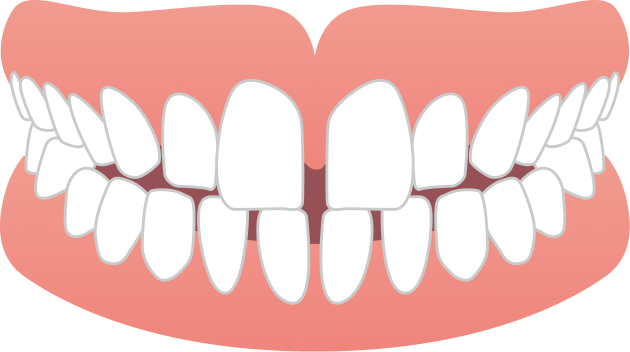

「前歯が出ているのが気になる」「前歯で噛めない」というお悩みでご来院されました。

BEFORE

| 主訴 | 出っ歯、前歯で噛めない(噛み合わせが悪い) |